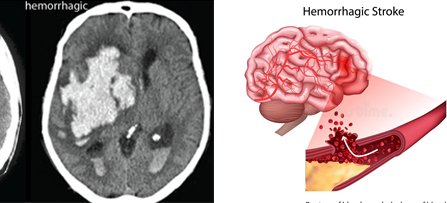

When an artery ruptures resulting in leaking of blood over the brain it is called a hemorrhagic stroke. The proper function of the brain is disturbed during a stroke, due to the lack of oxygen and nutrients to the brain cells.

HEMORRHAGIC STROKE

The main treatment is to control bleeding and resulting swelling. Generally, strict blood pressure control is required. In case of ballooning of arteries which ruptures and cause the bleed, surgical treatment may be required.